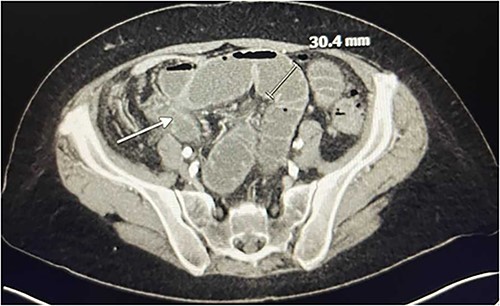

In the emergency department on presentation to our hospital, her vital signs were unremarkable and laboratory results were notable for a white blood cell count of 13 600 with left shift to 86% neutrophils. She underwent a computed tomography (CT) angiogram, which revealed an occluded SMA, severe celiac artery stenosis (nearly 90%), and a patent IMA (Fig. 1). A high-grade SBO was noted, possibly secondary to stricture, with transition point in the right lower quadrant (Fig. 2).

CT Angiography showing SBO with transition point in the right lower quadrant. A loop of thickened ileum measures 30.4 mm. The white arrow points to a stricture.